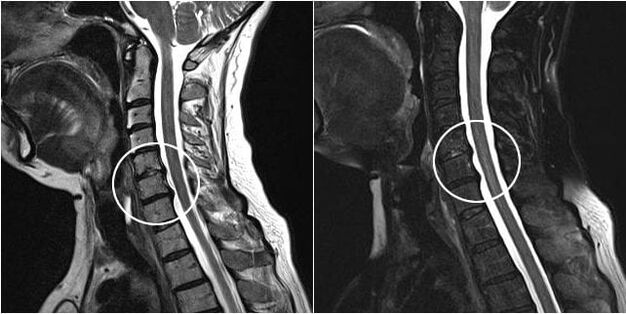

MRI

Magnetic resonance imaging is a diagnostic method that allows the creation of a multilayer image in several projections, but is in no way related to the use of X-rays. It is based on magnetic resonance, so it is safer than X-rays and CT scans, but it is not suitable for patients with permanent metal structures in the body. In addition, this study is noisier and longer. Like CT, MRI can also be done with contrast for more accurate diagnosis of certain diseases.

- surgical intervention.In the case of a herniated disc, surgery may be prescribed if other pain relief methods do not bring results for a long time, and it is justified based on the results of MRI, X-ray or X-ray.